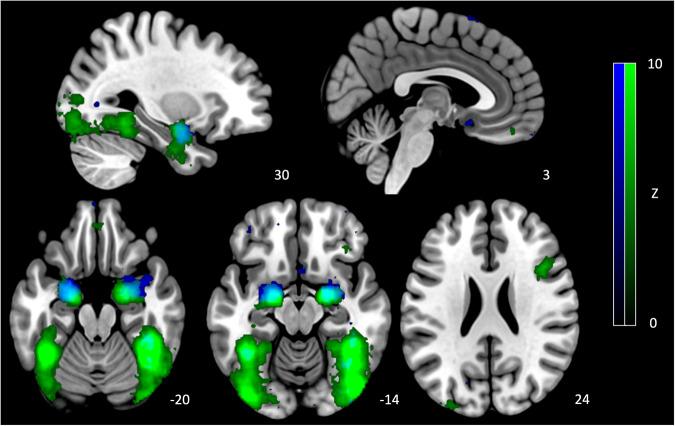

Major depressive disorder (MDD) is marked by altered processing of emotional stimuli, including facial expressions. Recent neuroimaging research has attempted to investigate how these stimuli alter the directional interactions between brain regions in those with MDD; however, methodological heterogeneity has made identifying consistent effects difficult. To address this, we systematically examined studies investigating MDD-associated differences present in effective connectivity during the processing of emotional facial expressions. We searched five databases: PsycINFO, EMBASE, PubMed, Scopus, and Web of Science, using a preregistered protocol (registration number: CRD42021271586). Of the 510 unique studies screened, 17 met our inclusion criteria. These studies identified that compared with healthy controls, participants with MDD demonstrated (1) reduced connectivity from the dorsolateral prefrontal cortex to the amygdala during the processing of negatively valenced expressions, and (2) increased inhibitory connectivity from the ventromedial prefrontal cortex to amygdala during the processing of happy facial expressions. Most studies investigating the amygdala and anterior cingulate cortex noted differences in their connectivity; however, the precise nature of these differences was inconsistent between studies. As such, commonalities observed across neuroimaging modalities warrant careful investigation to determine the specificity of these effects to particular subregions and emotional expressions. Future research examining longitudinal connectivity changes associated with treatment response may provide important insights into mechanisms underpinning therapeutic interventions, thus enabling more targeted treatment strategies.

重度抑郁症(MDD)的特征是对包括面部表情在内的情绪刺激的处理发生改变。最近的神经影像学研究试图探究这些刺激如何改变MDD患者大脑区域之间的定向相互作用;然而,方法学上的异质性使得确定一致的效应变得困难。为了解决这个问题,我们系统地审查了研究情绪性面部表情处理过程中有效连接性方面存在的MDD相关差异的研究。我们使用预先注册的方案(注册号:CRD42021271586)在五个数据库中进行了检索:PsycINFO、EMBASE、PubMed、Scopus和Web of Science。在筛选的510项独特研究中,有17项符合我们的纳入标准。这些研究表明,与健康对照相比,MDD患者在处理负性情绪表情时,从背外侧前额叶皮质到杏仁核的连接性降低,以及在处理开心面部表情时,从腹内侧前额叶皮质到杏仁核的抑制性连接性增加。大多数研究杏仁核和前扣带回皮质的研究都指出了它们连接性的差异;然而,这些差异的确切性质在不同研究之间并不一致。因此,在不同神经影像学模式中观察到的共性值得仔细研究,以确定这些效应针对特定亚区域和情绪表情的特异性。未来研究检查与治疗反应相关的纵向连接性变化,可能会为治疗干预的潜在机制提供重要见解,从而实现更有针对性的治疗策略。